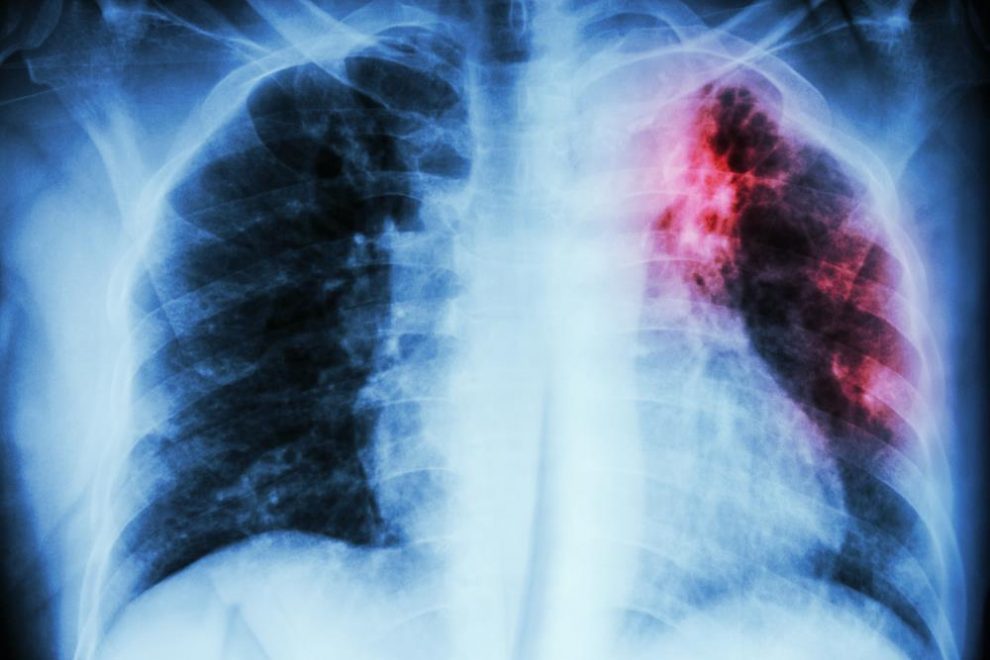

Pain Under Rib Cage Pneumonia . A person should get immediate medical attention if pain beneath the right rib cage is severe, reoccurring, or accompanied by the following symptoms: Find out the most common causes of pain in right side under ribs, including when to see a doctor and when to use home treatments to relieve and prevent the rib cage pain. Pleurisy on your left side may cause pain under your left rib cage, but the main symptom is a sharp, stabbing pain when you. This is often due to labored breathing. Pneumonia is an infection that inflames the air sacs in one or both lungs. The air sacs may fill with fluid or pus (purulent material), causing cough with phlegm or pus, fever,. Wheezing is common, especially with viral pneumonia. Pain below your ribs can be caused by your gi tract, like gerd, indigestion, gallbladder disease, or constipation, or problems with your lungs, like pneumonia. This is signaled by a bluish appearance to a child's lips, nose, and fingers, which means there's not enough oxygen in the blood. Understanding the potential causes of pain under or around the left rib cage is crucial for prompt diagnosis and appropriate treatment.

Understanding the potential causes of pain under or around the left rib cage is crucial for prompt diagnosis and appropriate treatment. Pain below your ribs can be caused by your gi tract, like gerd, indigestion, gallbladder disease, or constipation, or problems with your lungs, like pneumonia. This is often due to labored breathing. Pneumonia is an infection that inflames the air sacs in one or both lungs. The air sacs may fill with fluid or pus (purulent material), causing cough with phlegm or pus, fever,. A person should get immediate medical attention if pain beneath the right rib cage is severe, reoccurring, or accompanied by the following symptoms: Wheezing is common, especially with viral pneumonia. This is signaled by a bluish appearance to a child's lips, nose, and fingers, which means there's not enough oxygen in the blood. Pleurisy on your left side may cause pain under your left rib cage, but the main symptom is a sharp, stabbing pain when you. Find out the most common causes of pain in right side under ribs, including when to see a doctor and when to use home treatments to relieve and prevent the rib cage pain.